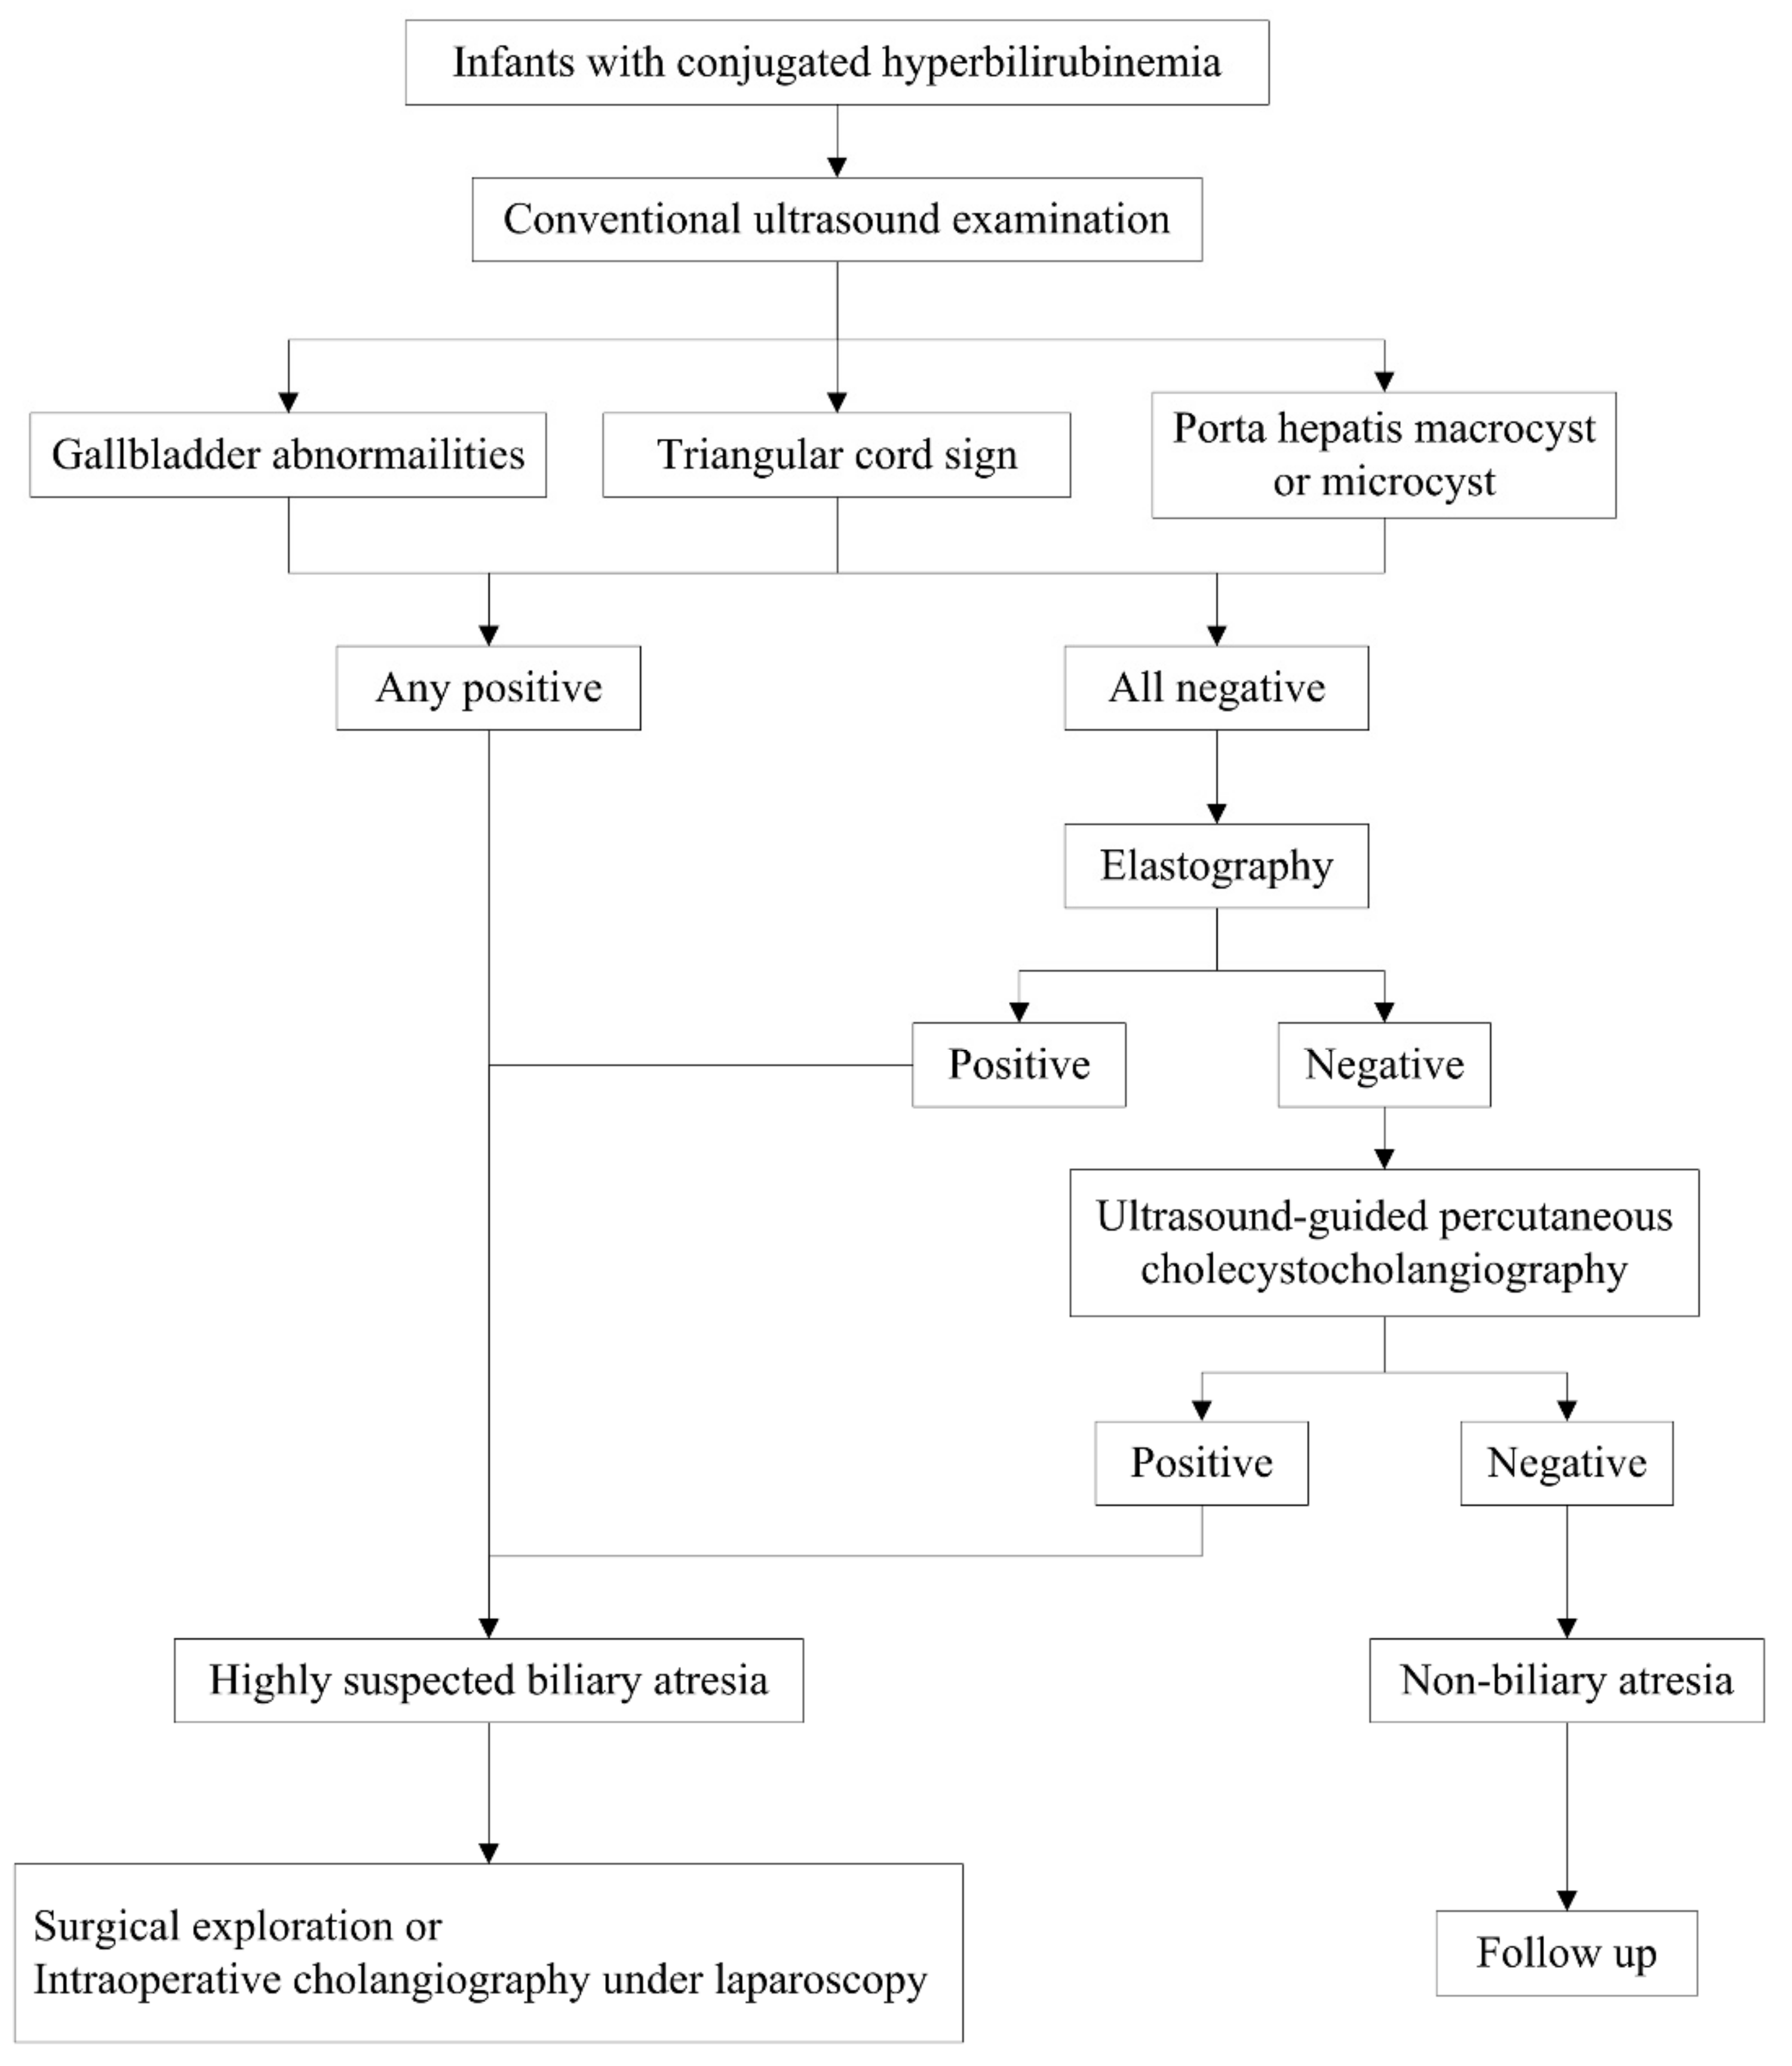

2. Conventional Ultrasound

2.1. Gallbladder Abnormalities

2.2. Triangular Cord Sign

2.3. Porta Hepatis Macro- or Microcyst

2.4. Enlarged Hepatic Hilar Lymph Node (LN)

2.5. Other Helpful US Features

3. Elastography

4. US-Guided Percutaneous Cholecystocholangiography with Microbubbles

6. Summary